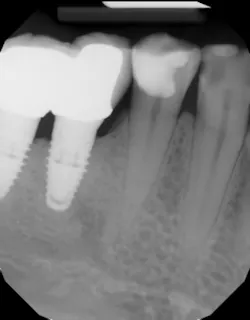

It is imperative for clinicians and teams involved with dental implant care to be aware of implant-induced decay, take necessary radiographs, and perform clinical exams in order to identify open contacts prior to caries development. Once teeth adjacent to implants are afflicted with decay, restoration (figure 2) or even extraction may be warranted (figure 3). To prevent these problems from occurring, individuals who have contributing factors mentioned in this article may benefit from having a screw-retained implant restoration and/or be given an Essix appliance to prevent tooth migration.

Figure 2: This decayed tooth adjacent to an implant requires restoration.